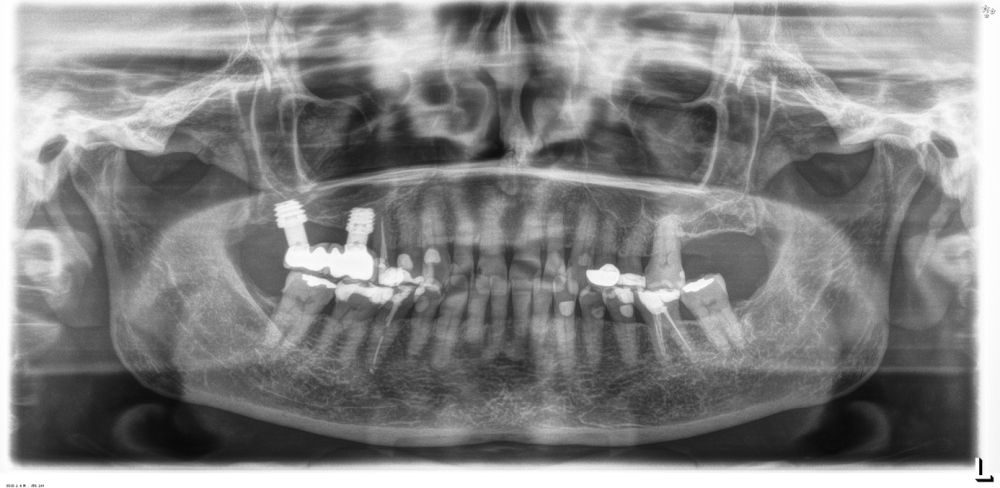

Resultados. Fueron reclutados 13 pacientes en los que se insertaron 30 implantes. Una vez insertados y cargados los implantes, la altura media final fue de 9,68 mm (+/- 2,66), lo que supone una ganancia promedio de 5 mm. A los 10 años, se observó una disminución media de la altura ósea ganada en los implantes en conjunto de 0, 29 mm (+/- 0,77). La media de la pérdida ósea mesial fue de 0,73 mm (+/- 0,75 mm) y la media de la pérdida ósea distal fue de 0,98 mm (+/- 1,2 mm). La supervivencia fue del 100%.

Results.Thirteen patients were recruited and 30 implants were inserted. Once the implants were inserted and loaded, the mean final height was 9.68 mm (+/- 2.66), which represents an average gain of 5 mm. At 10 years, there was a mean decrease in the overall bone height gain of the implants of 0.29 mm (+/- 0.77). The mean mesial bone loss was 0.73 mm (+/- 0.75 mm) and the mean distal bone loss was 0.98 mm (+/- 1.2 mm). Survival was 100%.

Los senos tratados con la técnica de elevación transcrestal sin material de relleno muestran un incremento de entre 2,5 mm12,13 hasta 4.4 mm14,15 en la altura ósea lograda sobre el ápice y una supervivencia de los implantes que se sitúa entre un 94 y un 100%16-17. En este trabajo se presenta un estudio retrospectivo donde se ha evaluado la inserción de implantes extracortos (5,5 y 6,5 mm) en zonas posteriores maxilares mediante la técnica de elevación de seno transcrestal con la fresa de ataque frontal sin la utilización de material de injerto, con un tiempo de seguimiento de 10 años para poder objetivar el comportamiento de los implantes a largo plazo y de la técnica empleada.